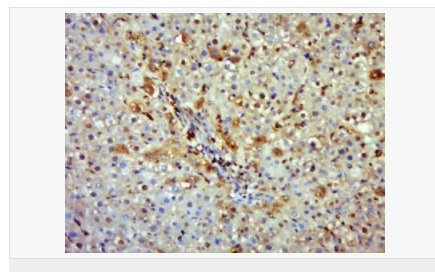

| 產(chǎn)品介紹 | Nitric oxide (NO) is an inorganic, gaseous free radical that carries a variety of messages between cells. Vasorelaxation, neurotransmission and cytotoxicity can all be potentiated through cellular response to NO. NO production is mediated by members of the nitric oxide synthase (NOS) family. NOS catalyzes the oxidization of L-arginine to produce L-citrulline and NO. Two constitutive isoforms, brain or neuronal NOS (b or nNOS, type I) & endothelial cell NOS (eNOS, type III), and one inducible isoform (iNOS, type II), have been cloned. All NOS isoforms contain calmodulin, nicotinamide adenine dinucleotide phosphate (NADPH), flavin adenine dinucleotide (FAD), and flavin mononucleotide (FMN) binding domains. Nitric oxide synthase is expressed in liver, macrophages, hepatocytes, synoviocytes, stimulated glial cells and smooth muscle cells. Cytokines such as interferon-gamma (IFN), tumor necrosis factor (TNF), interleukin-1 and -2, and lipopolysaccarides (LPS) cause an increase in iNOS mRNA, protein, and activity levels. Protein kinase C-stimulating agents exhibit the same effect on iNOS activity. After cytokine induction, iNOS exhibits a delayed activity response which is then followed by a significant increase in NO production over a long period of time. Human iNOS is regulated by calcium/calmodulin (in contrast with mouse NOS2). Function: Produces nitric oxide (NO) which is a messenger molecule with diverse functions throughout the body. In macrophages, NO mediates tumoricidal and bactericidal actions. Also has nitrosylase activity and mediates cysteine S-nitrosylation of cytoplasmic target proteins such COX2. Subunit: Homodimer. Binds SLC9A3R1. Tissue Specificity: Expressed in the liver, retina, bone cells and airway epithelial cells of the lung. Not expressed in the platelets. Similarity: Belongs to the NOS family. Contains 1 FAD-binding FR-type domain. Contains 1 flavodoxin-like domain. SWISS: P35228 Gene ID: 4843 Database links: Entrez Gene: 4843 Human Entrez Gene: 18126 Mouse Omim: 163730 Human SwissProt: P35228 Human SwissProt: P29477 Mouse Unigene: 709191 Human Unigene: 2893 Mouse Unigene: 10400 Rat Important Note: This product as supplied is intended for research use only, not for use in human, therapeutic or diagnostic applications. 合成與降解(Synthesis and Degradation) 催化生物體內一氧化氮(NO)生成的酶。分神經(jīng)型一氧化氮合成的酶(nNOS or NOS-1)、誘導型一氧化氮合成的酶(iNOS or NOS-2)、內皮型一氧化氮合成的酶(eNOS or NOS-3)。 |